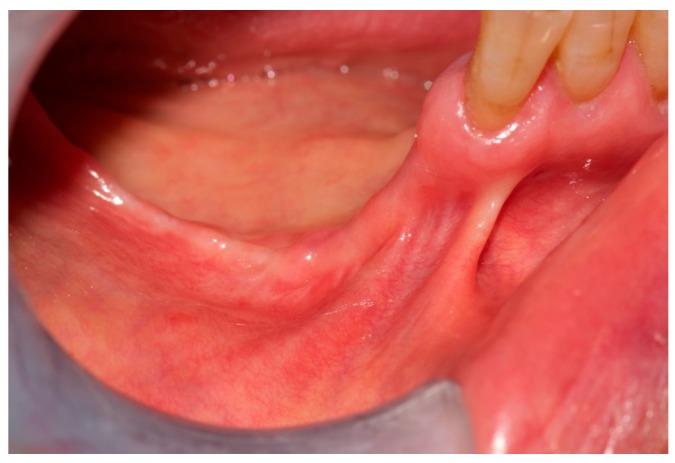

Osteonecrosis of the jaws (ONJ) in osteoporosis patients has been defined as rare, but the number of reported cases is increasing. We report a case of delayed ONJ diagnosis in a patient, who was being treated with alendronate, developing bone alterations both in maxilla and in mandible. Underestimation of ONJ incidence and missed or delayed ONJ diagnosis in osteoporosis patients might derive from lack of awareness of health providers as well as from an ONJ definition that is too restricted. The more recent definition of medication-related osteonecrosis of the jaws (MRONJ) released in 2014 by the American Association of Oral Maxillofacial Surgeons (AAOMS) accept fistula, besides bone exposure, as a major sign of disease, but it seems to be insufficient since it excludes all cases of ONJ disease without bone exposure. A new MRONJ definition is needed to avoid missing or delayed diagnosis.

骨质疏松症患者颌骨骨坏死(ONJ)一直被定义为罕见病,但报告的病例数量正在增加。我们报告了一例接受阿仑膦酸盐治疗的患者ONJ诊断延迟的病例,该患者上颌骨和下颌骨均出现骨质改变。骨质疏松症患者中ONJ发病率的低估以及ONJ诊断的漏诊或延迟,可能源于医疗服务提供者认识不足以及ONJ定义过于局限。美国口腔颌面外科医师协会(AAOMS)2014年发布的与药物相关的颌骨骨坏死(MRONJ)的最新定义,除了骨暴露外,还将瘘管视为疾病的主要体征,但这似乎并不充分,因为它排除了所有无骨暴露的ONJ病例。需要一个新的MRONJ定义以避免漏诊或延迟诊断。